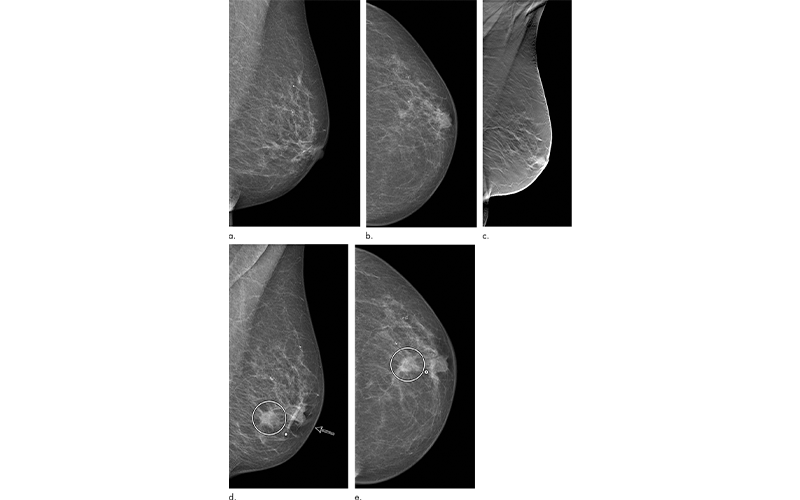

Images in a 72-year-old woman who was diagnosed with a 13-mm lymph node-negative invasive lobular carcinoma luminal B–like human epidermal growth factor receptor 2 breast cancer 18 months after a screening negative for cancer in the Malmö Breast Tomosynthesis Screening Trial. (a) Mediolateral oblique and (b) craniocaudal digital mammography (DM) images at screening. The slight retraction of the nipple was unchanged compared with previous DM screening images. c) Digital breast tomosynthesis at screening. DM images of (d) mediolateral oblique and (e) craniocaudal views at diagnosis, small marker at lump location. Increased nipple retraction (arrow) and central mass (circle on d and e).